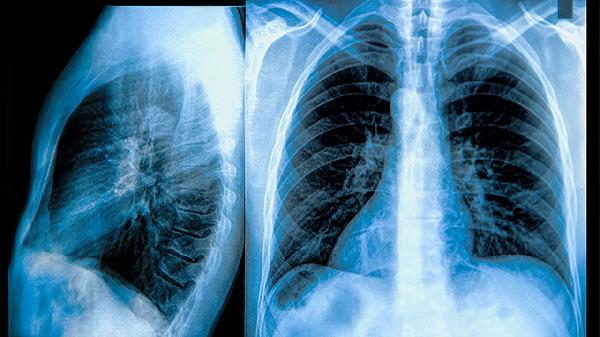

肺结节在CT检查中被判定为良性通常意味着这些结节并不具备恶性肿瘤的特征。尽管如此,仍然建议患者尽快就医,在医生的指导下进行进一步的检查,以明确诊断并制定适当的治疗方案。这不仅有助于确定结节的性质,还能为后续的健康管理提供依据。